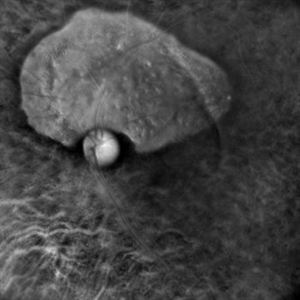

Collar Button Appearance on B-Scan

Aug 28 2019 by Gayathri Mohan

B-scan showing an intraocular mass with collar button appearance. Suspected case of choroidal melanoma.

Photographer: Dr.Gayathri Mohan, Retina Foundation

Imaging device: Nidek Mirante SLO

Condition/keywords: choroidal mass, collar button